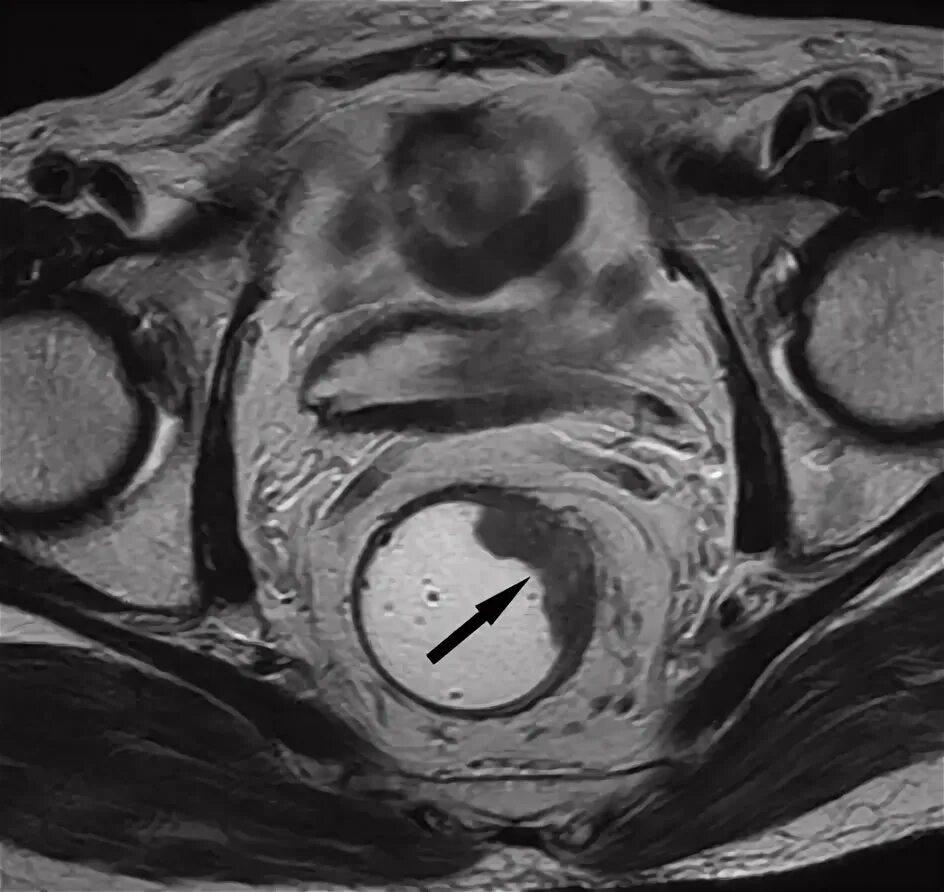

Мрт симптомы